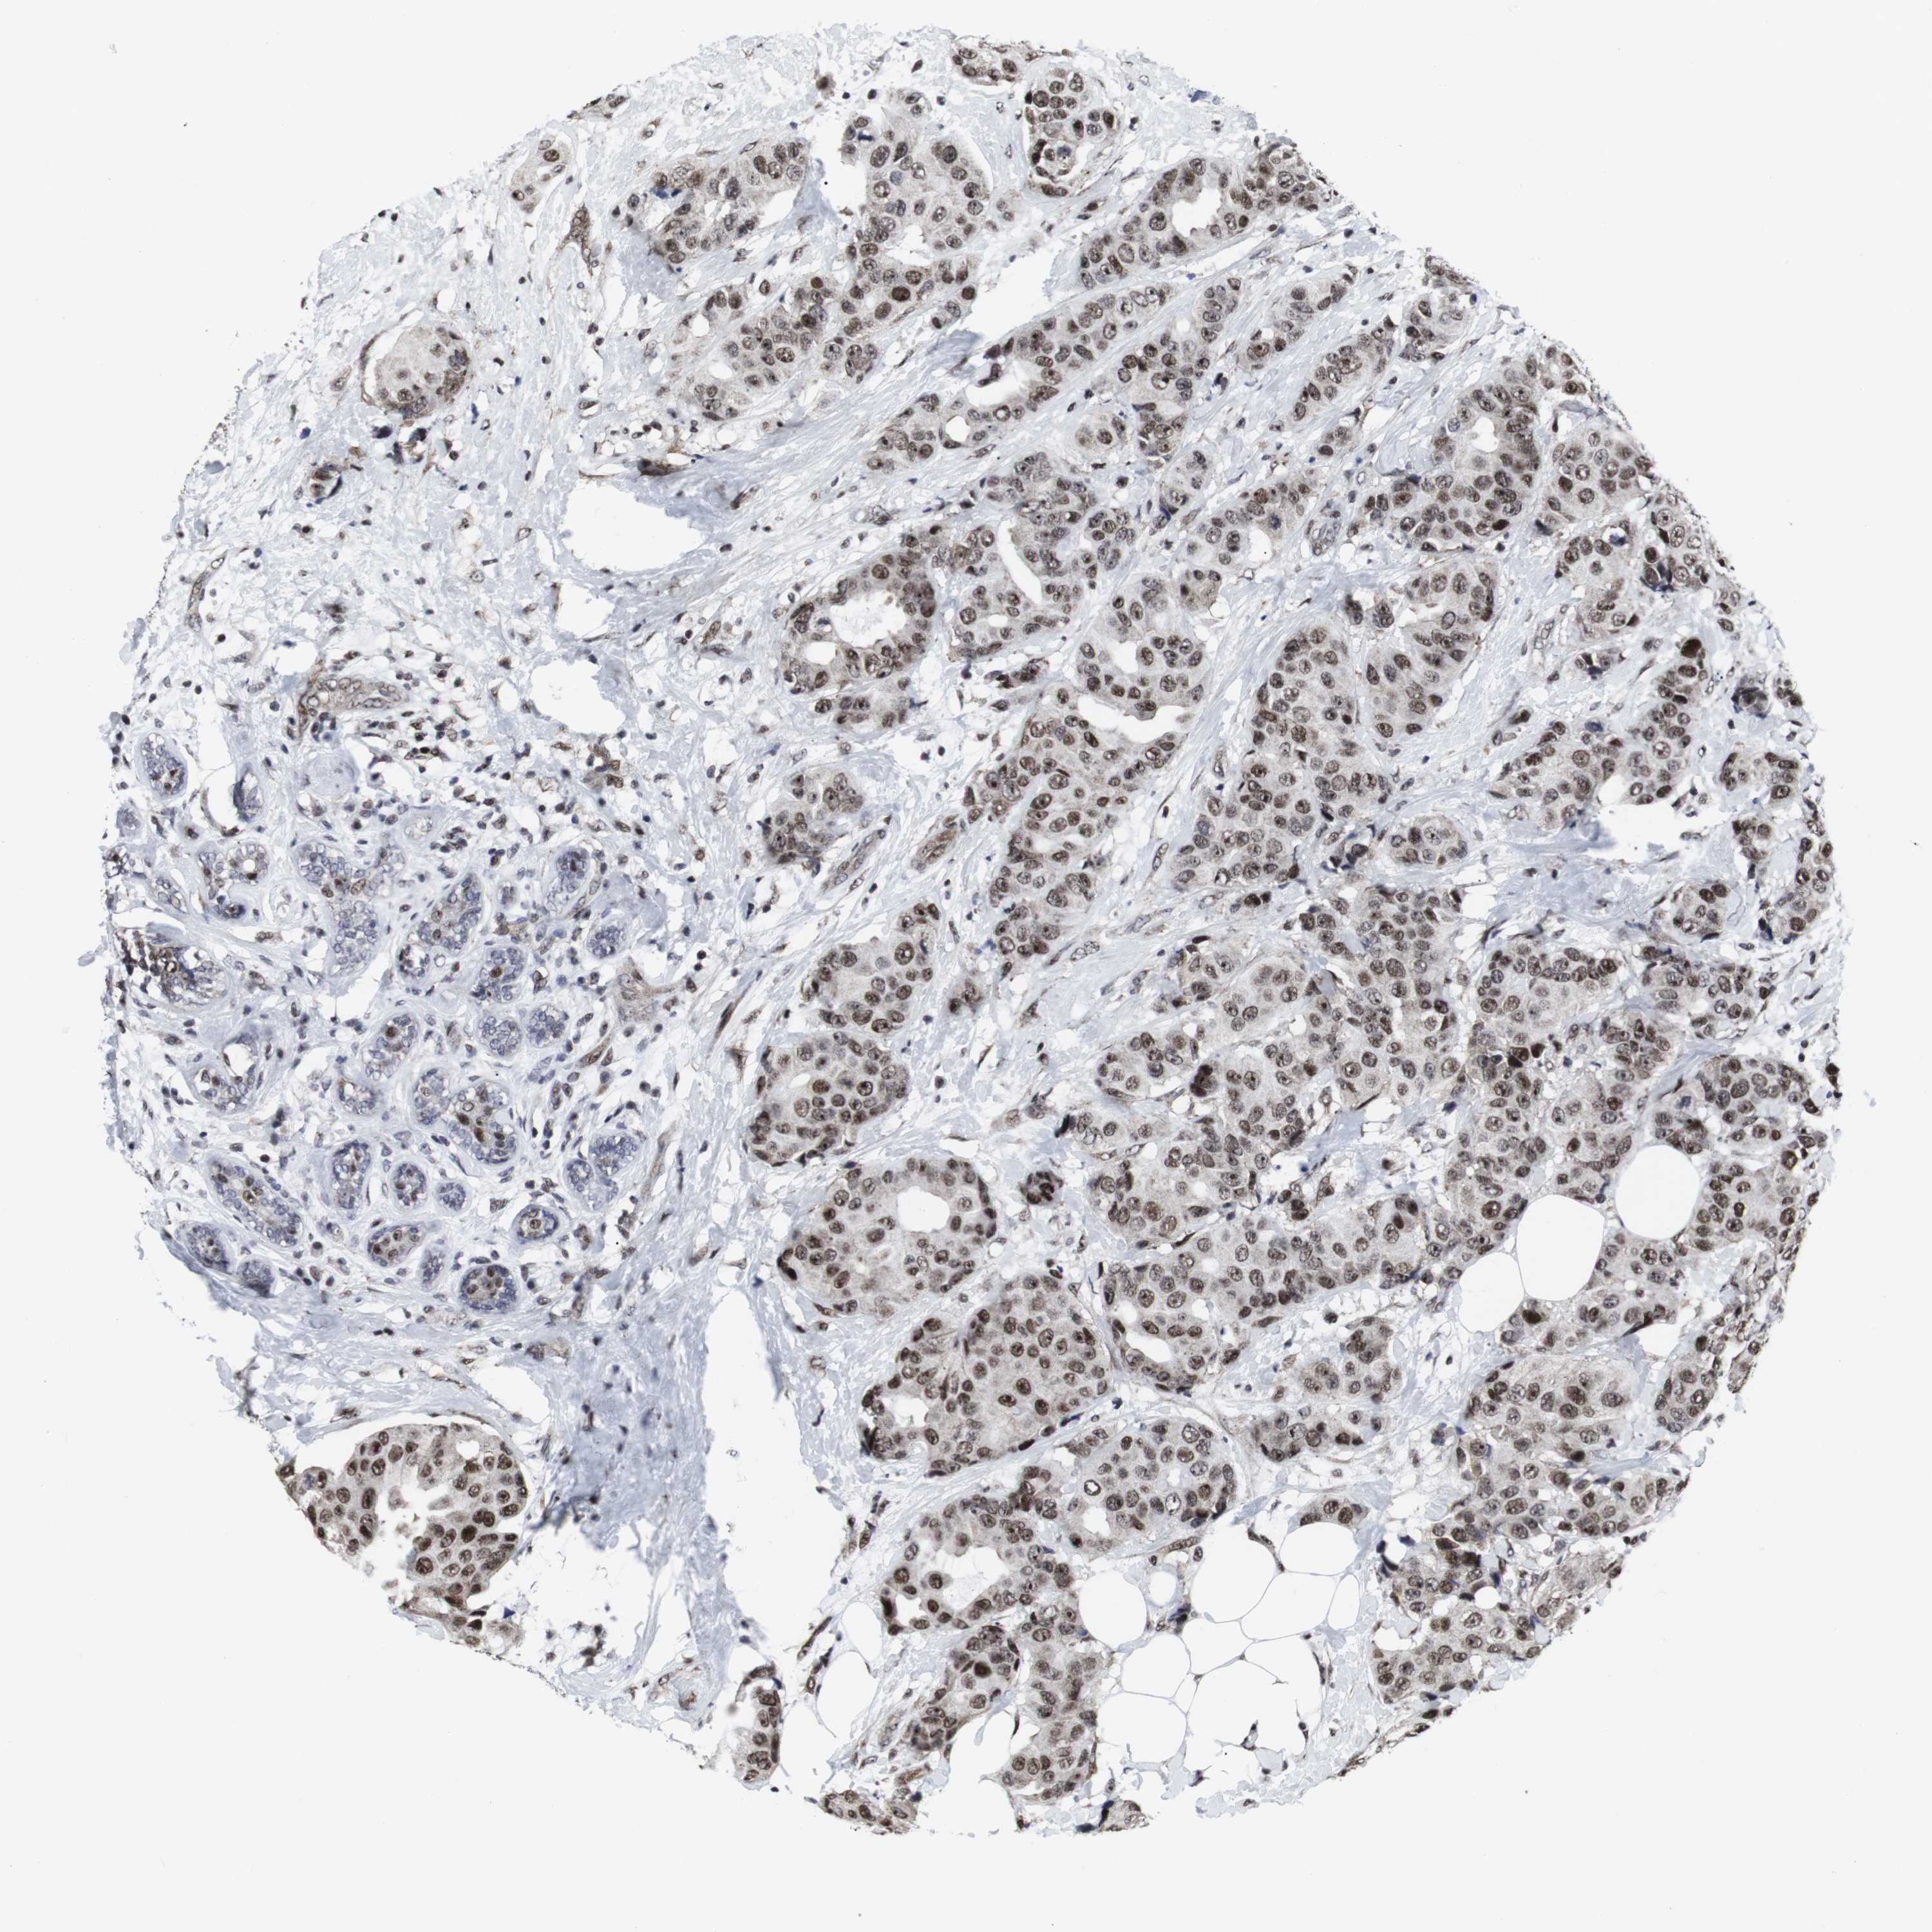

CANCER BREAST CANCER Show tissue menu

BRCA TCGA BRCA VALIDATION PROTEIN EXPRESSION